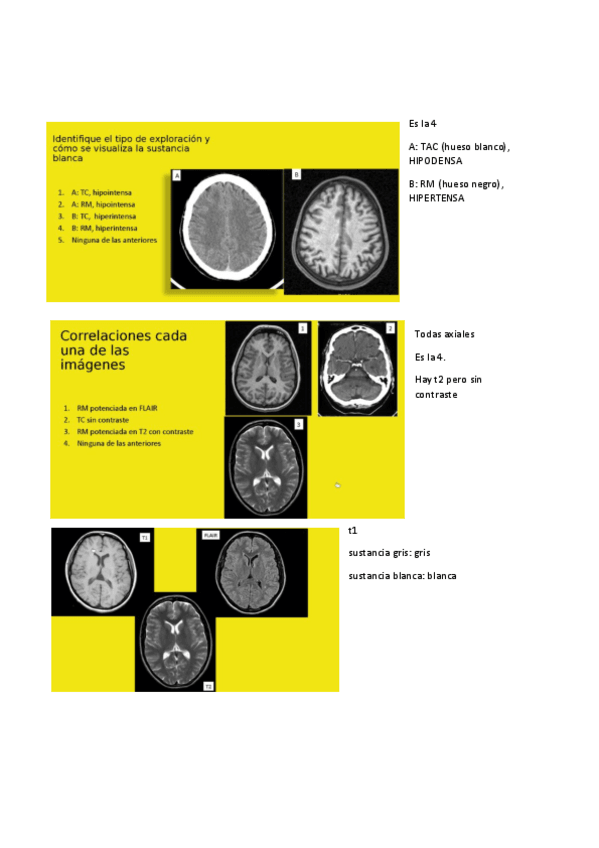

SEMINARIO-RADIOLOGIA-NEURO.pdf

Apuntes - SEMINARIO-RADIOLOGIA-NEURO.pdf